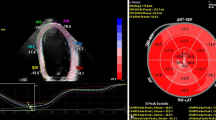

Right ventricular myocardial strain was measured blinded for randomization outcome in the 4 chamber longitudinal axis images using commercially available FT-CMR software (QStrain, Medis Medical Imaging Systems version 2.0.12.2, Leiden, The Netherlands) under the supervision of an experienced CMR cardiologist (JE, supervision AH). The right ventricular endocardial contours were drawn manually during the end-diastolic and end-systolic phase. Subsequently, the software automatically traced the cardiac contours during the cardiac cycle, resulting in the peak global longitudinal strain (GLS) of the entire right ventricle, GLS of the RV free wall (FWLS) and GLS of the septum. Since deformation of the intraventricular septum is considered to be mainly affected by LV dysfunction, we chose to focus on the total RV GLS and the RV FWLS, rather than GLS of the septum [18]. RV volumes were measured in the short axis images and corrected for body-surface area (AvV, supervision AH). For the calculation of the TAPSE, we measured the RV length in the 4 chamber longitudinal axis from the apex to the juncture of the tricuspid annulus with the RV free wall in end-diastole (end-diastolic length; EDL) and end-systole (end-systolic length; ESL), as described previously [19]. Then, the TAPSE was calculated by subtracting the ESL from the EDL. An example of the measurement techniques is displayed in Fig. 2.

Measurement of right ventricular function parameters. A and B End-diastolic length (A) and end-systolic length (B) measurement for the calculation of the tricuspid annular plane systolic excursion; C Right ventricular strain measurement using feature tracking, with the green line indicating tracking of the free wall and white line indicating the septum tracking; D Strain curves, with the upper curve indicating the general RV strain curve and the lower curve indicating the RV strain curves divided into septum (white), average (white) and free wall (green). eS indicates end-systolic and eD indicates end-diastolic; E, F Right ventricular contours in the short-axis end-diastole (E) and end-systole (F) for RV volume measurements